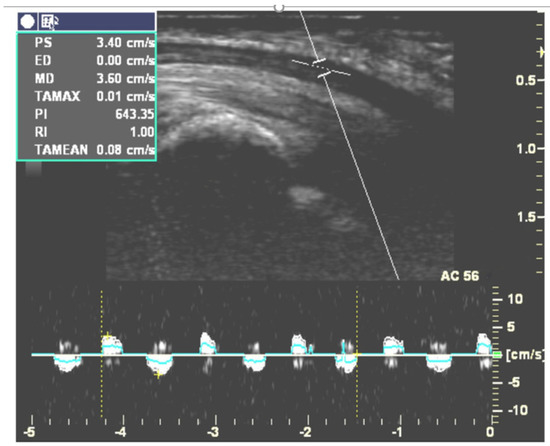

Figure 2. Doppler waveforms for measuring longitudinal MN gliding during active flexion and the extension cycle of the index finger at a speed of one time per second. (This figure was adapted from Liu et al. [33]).

Five studies targeting longitudinal gliding of the MN are described in Table 4. Two [30,33] of them used duplex Doppler to evaluate longitudinal gliding of the MN by adjusting the Doppler sample volume indicator to lie within the MN (Figure 2). They recorded the Doppler waveform while subjects continuously moved their fingers and calculated the area under the Doppler waveform in the velocity-time integral (VTI) spectrum. This area represented the amount of longitudinal MN gliding during each cycle of finger movement [55]. Hough et al. found that CTS patients had less MN gliding than healthy controls during elbow extension but not during elbow flexion [30]. Liu et al. [33] measured longitudinal MN gliding in both the neutral and 30 degree wrist extension positions. Their results revealed that the ratio of the gliding of the MN to the flexor tendon was significantly smaller in CTS patients than in healthy volunteers. They also found that gliding of the MN was significantly increased while extending the wrist joint to 30 degrees in CTS patients [33]. The other three studies recorded B-mode dynamic ultrasonography while subjects performed the target movements and used a cross-correlation algorithm or speckle-tracking algorithm to evaluate MN gliding frame-by frame [29,31,32]. For example, Erel et al. [29] analyzed longitudinal MN gliding at the forearm level during passive motion of the metacarpophalangeal joint, but their results did not demonstrate a significant difference in MN gliding between the CTS and control groups. In contrast, Filius et al. [31] demonstrated less longitudinal MN gliding in CTS patients. Filius et al. also published another article [32] exploring the relationship between tendon excursion velocity and longitudinal MN gliding. They found that the higher the moving velocity of the fingers, the greater the MN glided; moreover, MN gliding was reduced in the CTS group whenever fingers were moving at high or low speed.

Duplex Doppler is an alternative way to track longitudinal MN gliding. However, it is unable to capture out-of-plane movements caused by transverse movement beyond the beam width. Moreover, spectral broadening is an important artifact in pulsed-wave Doppler ultrasonographic imaging; therefore, the results might overestimate the MN excursions if the intrinsic spectral broadening was not accurately corrected [30]. Thus, previous studies used the ratio of nerve excursion to tendon excursion to correct this factor [30,33]. To explore and quantify the discrepancy caused by different measurement methods, we recommend further studies to compare the MN gliding detected by duplex Doppler and CC or BSP.